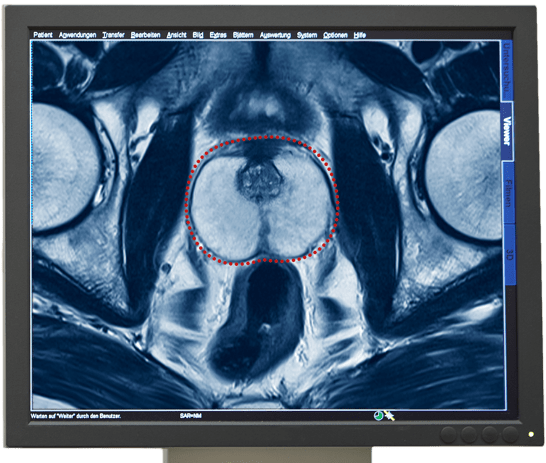

- Prostata mit Krebsherd

Het multiparmetrisch MRI-onderzoek van de Prostaat geldt als het zekerste beeldmateriaal om prostaatkanker te diagnosticeren. Met dit onderzoek kan een kankergezwel gevonden worden en de eigenschappen daarvan vastgesteld en beoordeeld worden.

De informatie over de kwaadaardigheid van een tumor wordt geleverd door een weefselanalyse. Daarvoor worden weefselbiopten uit het verdachte kankergezwel genomen. Met onze Prostaatbiopsie kunnen wij door MRI-sturing gerichte biopten uit het gezwel nemen, pathologisch onderzoeken en de Gleason-score bepalen.

Een multiparametrisch MRI-onderzoek van de prostaat kan de volgende informatie geven, die voor de aansluitende therapie behulpzaam kan zijn.

- Diagnose van de kwaadaardige tumor

- Plaats van de tumor

- Bepaling van de grote en volume van een tumor

- Expansie van de tumor

- Eventuele aantasting van de omliggende structuren of organen

- Eventuele aantasting van de lymfeknopen in het bekken

- Eventuele aanwezigheid van uitzaaiingen in de bekkenbeenderen